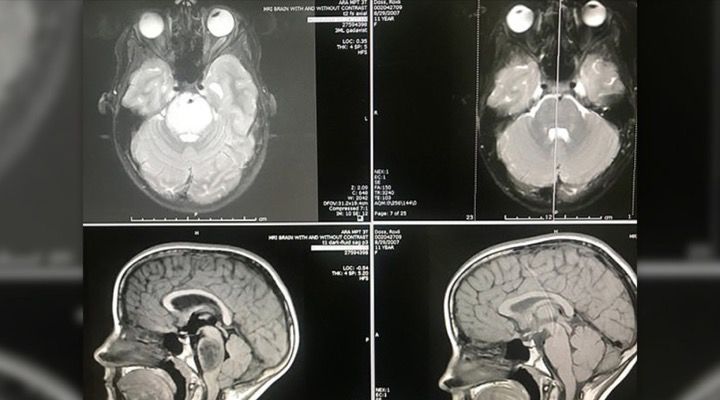

Actually Unbelievable

After six full weeks of radiation, despite the dire prognosis, Roxli was given an MRI and then went to visit her doctor, Dr. Harrod a few days later. “When I first saw Roxli’s MRI scan, it was actually unbelievable,” said Dr. Harrod. The tumor had totally disappeared and medical professionals, while ecstatic, were left scratching their heads in disbelief.

The tumor is inoperable due to being located at the base of the brain and at the top of the spine. The tumor presses on an area in the brain known as the pons which is responsible for some critical bodily functions such as breathing, sleeping and blood pressure.